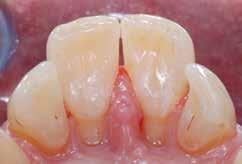

Presentazione del caso > F.V, bambino di cinque anni, presenta una malocclusione di II Classe scheletrica, III Classe dentale molare e canina destra e sinistra, morso inverso anteriore. Le arcate dentali mostrano usura degli elementi dentari anteriori a causa dell’occlusione patologica. Le linee mediane, superiore ed inferiore, sono centrate; il frenulo labiale superiore patologico per un’eccessiva estensione inter-incisale.

Dall’esame clinico si evince la III Classe dentale, l’inversione anteriore e l’over-jet negativo.